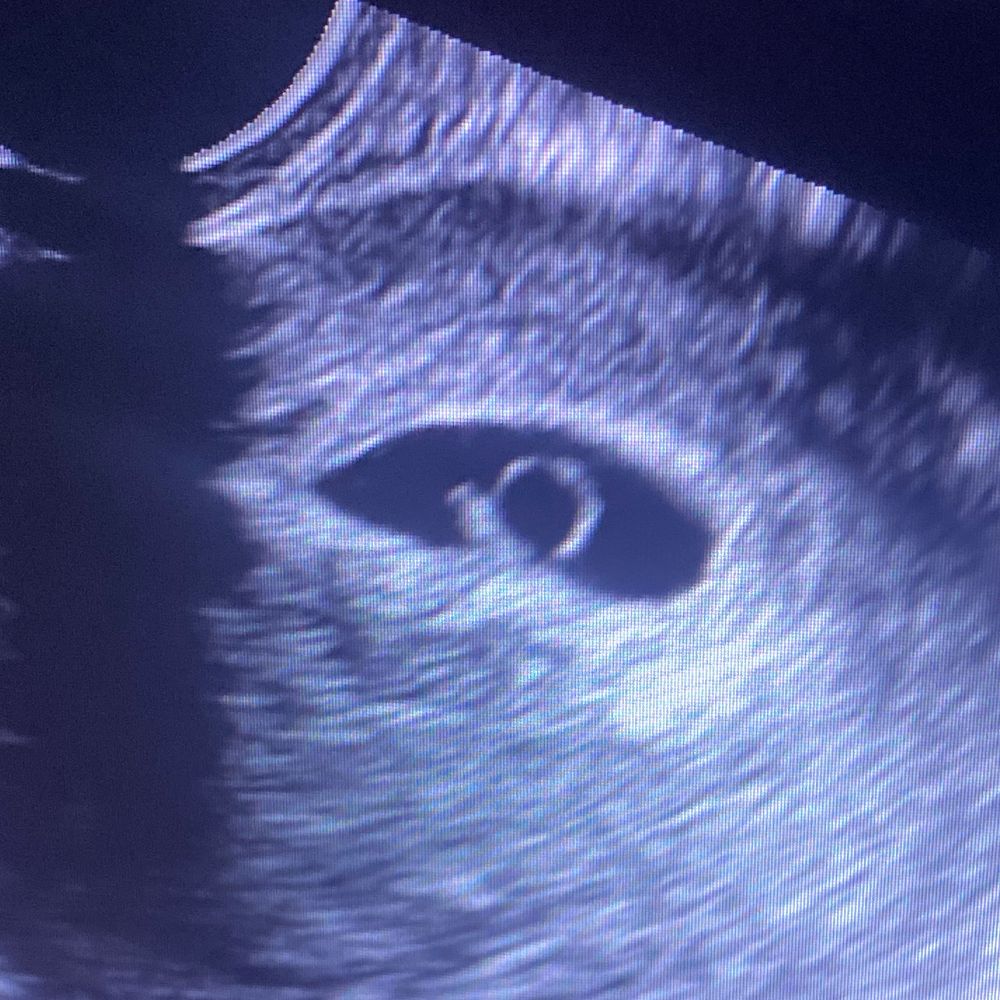

Затрудняюсь с категориейДевочки, привет. У меня сегодня 9.1 нед, 31 числа почувствовала недомогание, простыла( но тут такое дело, что буквально 1 числа грудь будто опала и стала не такой болезненной. Завтра на узи записалась, но не могу, вся прям как на иголках. Уже и сны всякие дурацкие снятся😭 неужели простуда и то, что грудь опала- просто совпадение?! Такая долгожданная беременность, я так очкую😭